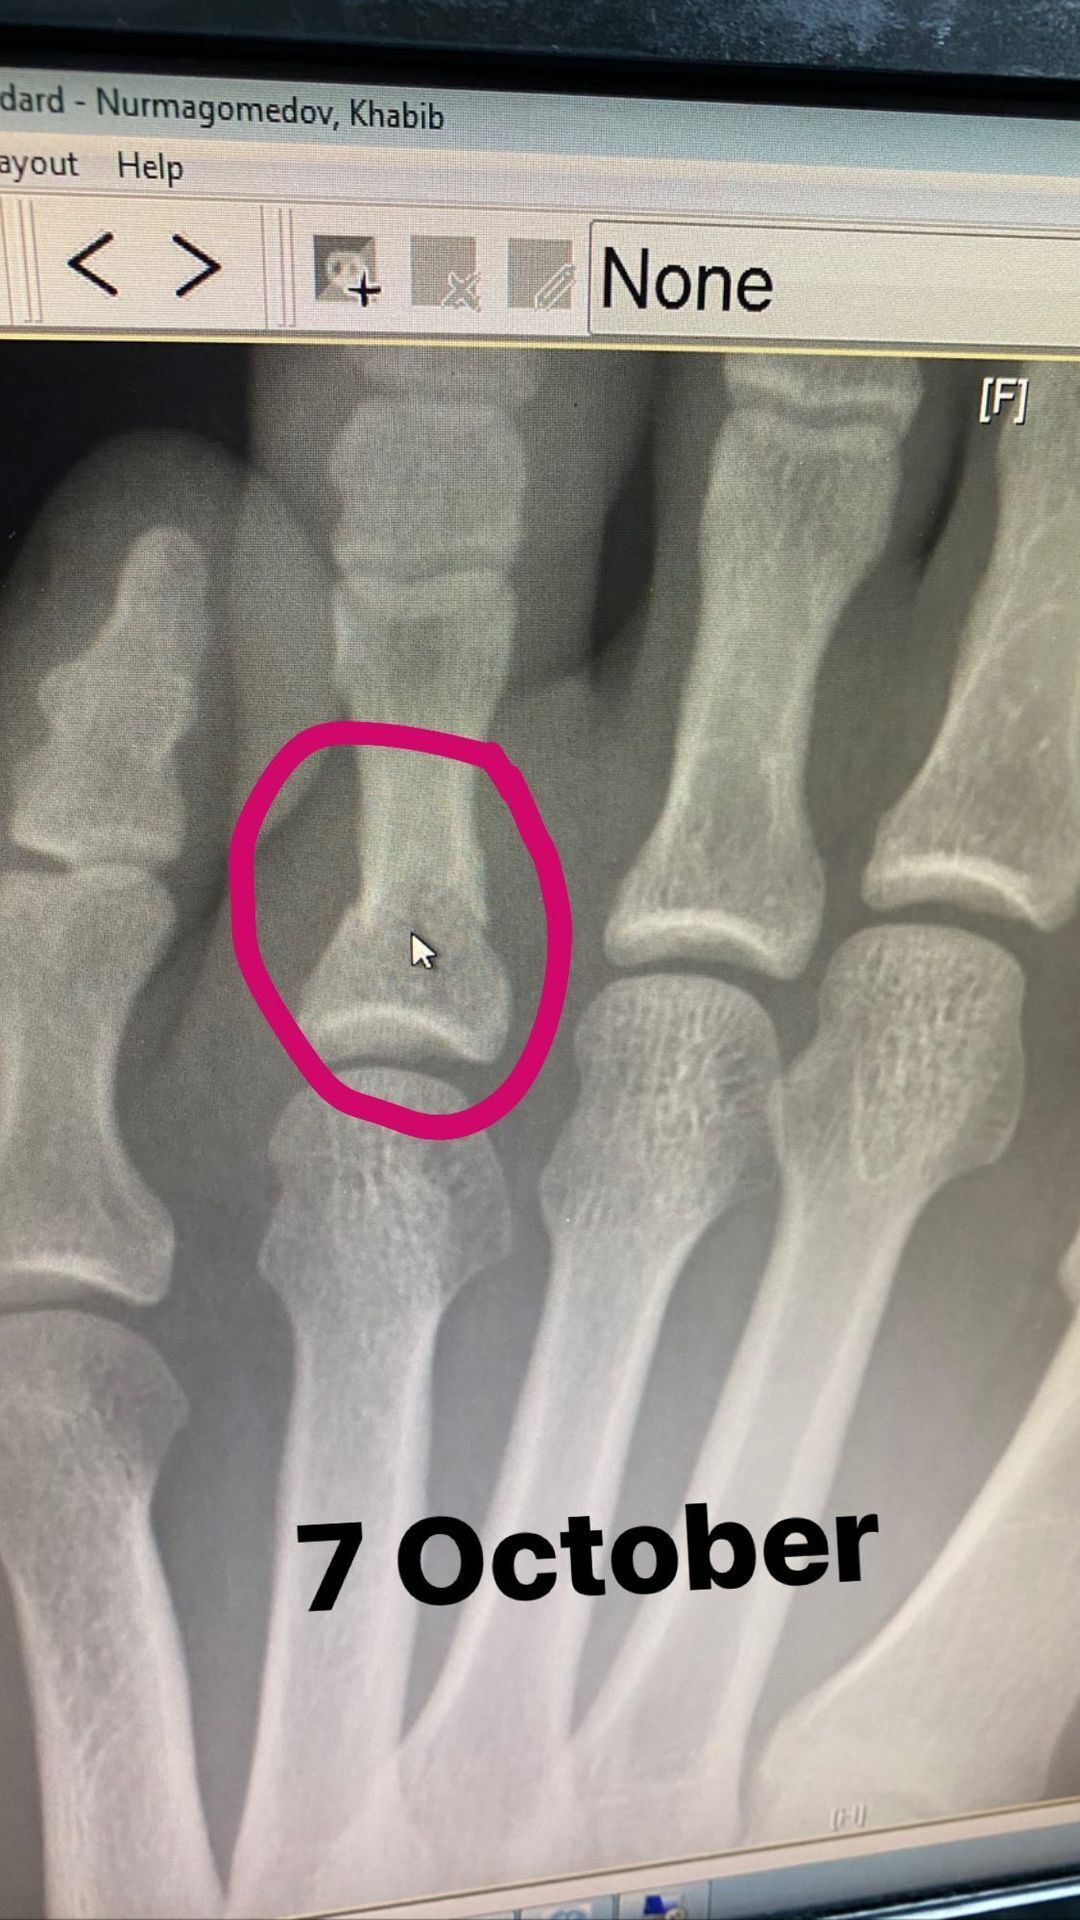

Він розповів, що спочатку хворів протягом двох тижнів, а потім зламав палець на нозі, тільки розпочавши тренування. У себе в Instagram-сторіз Нурмагомедов опублікував рентген-знімок, датований 7 жовтня, а також фотографію своєї ноги 8 жовтня.